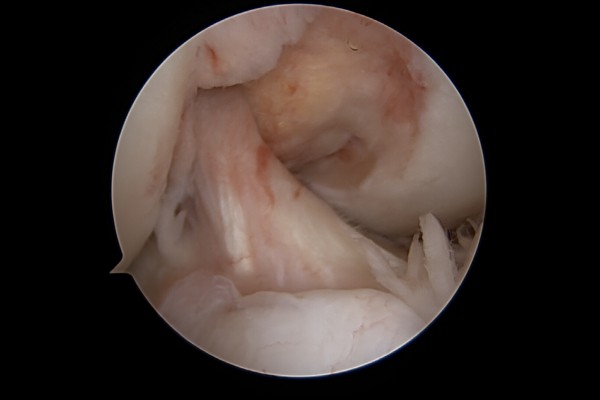

환자분의 무릎 상태를 파악하기 위해 X-RAY 촬영을 진행하였고, X-RAY에서 무릎 관절 사이에 유리체(뼛조각)가 확인됩니다.

관절내시경에서 유리체(뼛조각)이 확인됩니다.